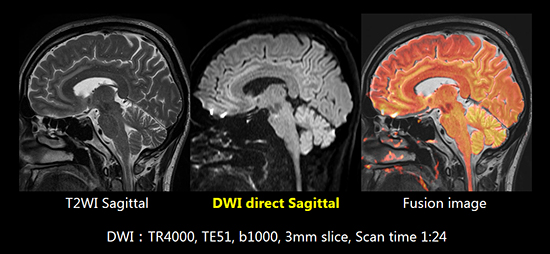

高精度Gradient

冷却能力や剛性を高めたGradientにより,ハイパワーでありながら渦電流の発生や発熱,振動を大幅に低減しました。Direct Sagittal撮像でも歪みの少ない拡散強調画像が得られます。